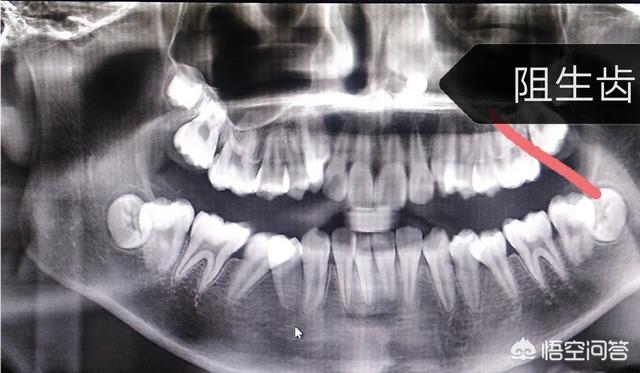

恒牙牙胚的位置异常

位置异常,乳牙牙根生理性吸收减少,脱落推迟,而恒压牙牙根在不断变长,一旦牙根到一定长度,就会动力不足,位置异常。遇到恒牙长出乳牙未脱落这样情况,根据乳牙松动情况决定采用表麻,还是浸润麻醉拔乳牙。

过软的饮食导致牙齿发育与颌骨发育不协调智齿阻生普遍。